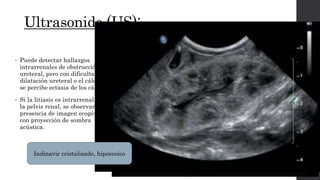

• Puede detectar hallazgos

intrarrenales de obstrucción

ureteral, pero con dificultad la

dilatación ureteral o el cálculo,

se percibe ectasia de los cálices.

• Si la litiasis es intrarrenal o en

la pelvis renal, se observará

presencia de imagen ecogénica

con proyección de sombra

acústica.

Indinavir cristalizado, hipoecoico

Riñón derecho con dilatación de grupos caliciales, pelvis renal y uréter proximal, observándose en

su interior una imagen ecogénica que mide 1,2 cm de diámetro con sombra acústica posterior.